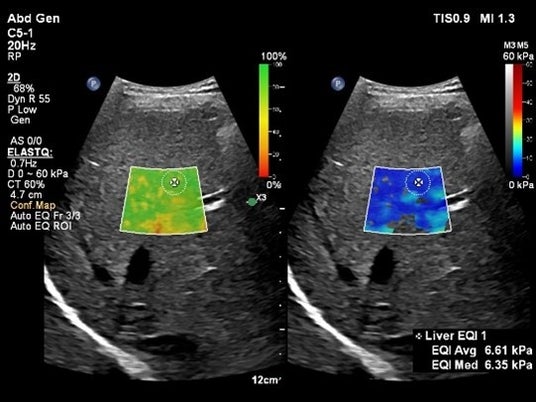

Shear Wave Elastographyを用いて肝臓の硬さを非侵襲的に計測するアプリケーションElastQ(エラストキュー)に、自動化機能が追加されました。Auto ElastQは、計測に適したフレームやROIポジションを自動で判別し、計測結果を表示することが可能です。これにより、これまで課題であった検査時間を最大60%短縮し[2]、99%の再現性が報告されています。[3]

Auto ElastQによる肝硬度の自動計測:適切なフレームとROIポジションが自動で判別され計測が行われます